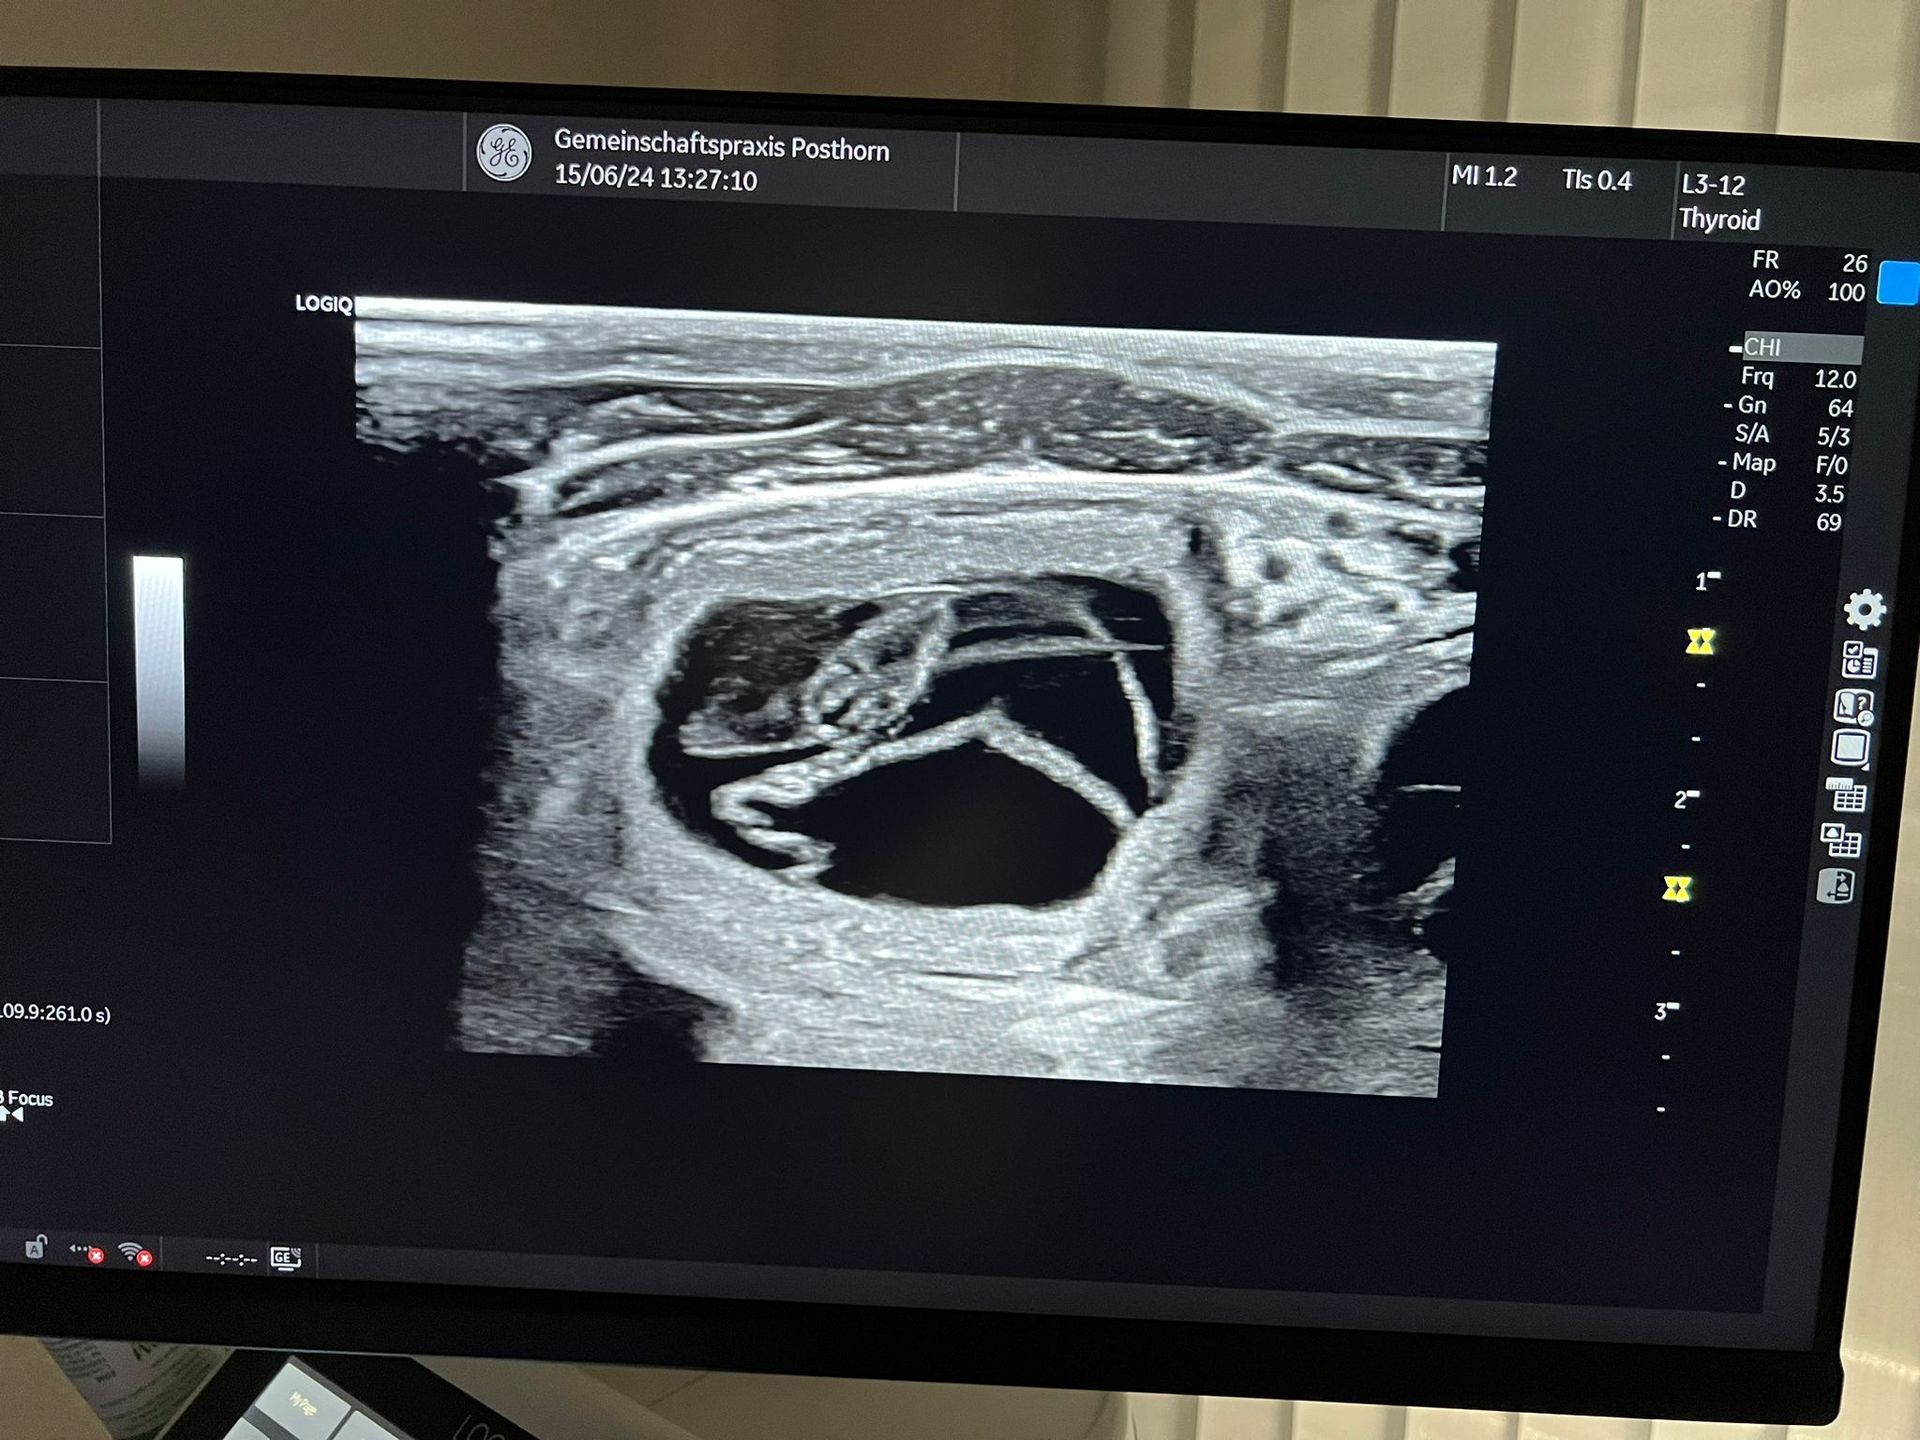

Wir freuen uns riesig, euch mitzuteilen, dass wir um den 18. Juli 2024 Welpen aus der Verpaarung von Real Love of Silken Flash und Dreams come true Dilani of bright jewels erwarten!